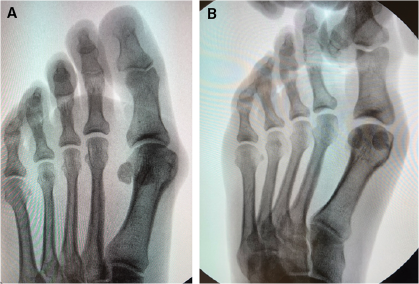

Saltzman and colleagues described how to radiographically evaluate the frontal plane rotation of the first metatarsal with use of a sesamoid axial X-ray.3 They define a line connecting the most inferior aspect of the medial edge of the medial sesamoid sulcus and the most inferior aspect of the lateral edge of the lateral sesamoid sulcus. The angle subtended by this “tangent” line and one parallel to the weightbearing platform determined the degree of metatarsal rotation.3

When performing a bunion correction surgery, surgeons often strive for frontal plane correction with physical rotation of the bone.1,2 One technique includes using a Kirschner wire (K-wire) as a joystick to rotate the direction of the osteotomy in the frontal plane out of valgus or eversion. In the senior author’s experience, when performing the minimally invasive technique for HAV, the frontal plane correction is a vitally important step.

When manipulating the hallux in the frontal plane, the surgeon can manually grasp and rotate the hallux and/or the distal first metatarsal (distal phalanx, proximal phalanx, distal metatarsal head and 2 seasmoids) as one unit/complex. By not performing a lateral release or performing any kind of dissection about the first metatarsophalangeal joint, one keeps the natural anatomy presented in valgus in malalignment intact, allows the entire complex (distal and proximal phalanges, sesamoids, and metatarsal head) to function as one unit, and avoids destabilizing the soft tissue attachments. Fluoroscopy can help one to observe the desired frontal plane rotation. Once obtaining the desired reduction in all planes, a K-wire can provide temporary fixation. Next, a screw may be inserted from proximal-medial to distal-lateral for permanent fixation.

Overall, we feel that surgeons should not neglect correction in the frontal plane when undertaking MIS procedures for HAV. In the senior author’s experience, this goal is achievable through manual reduction of the appropriate aspects of the distal first metatarsal after completing the MIS osteotomy. Fluoroscopy is valuable in evaluating and verifying correction, and the benefits of not performing a lateral release outweigh the risks.